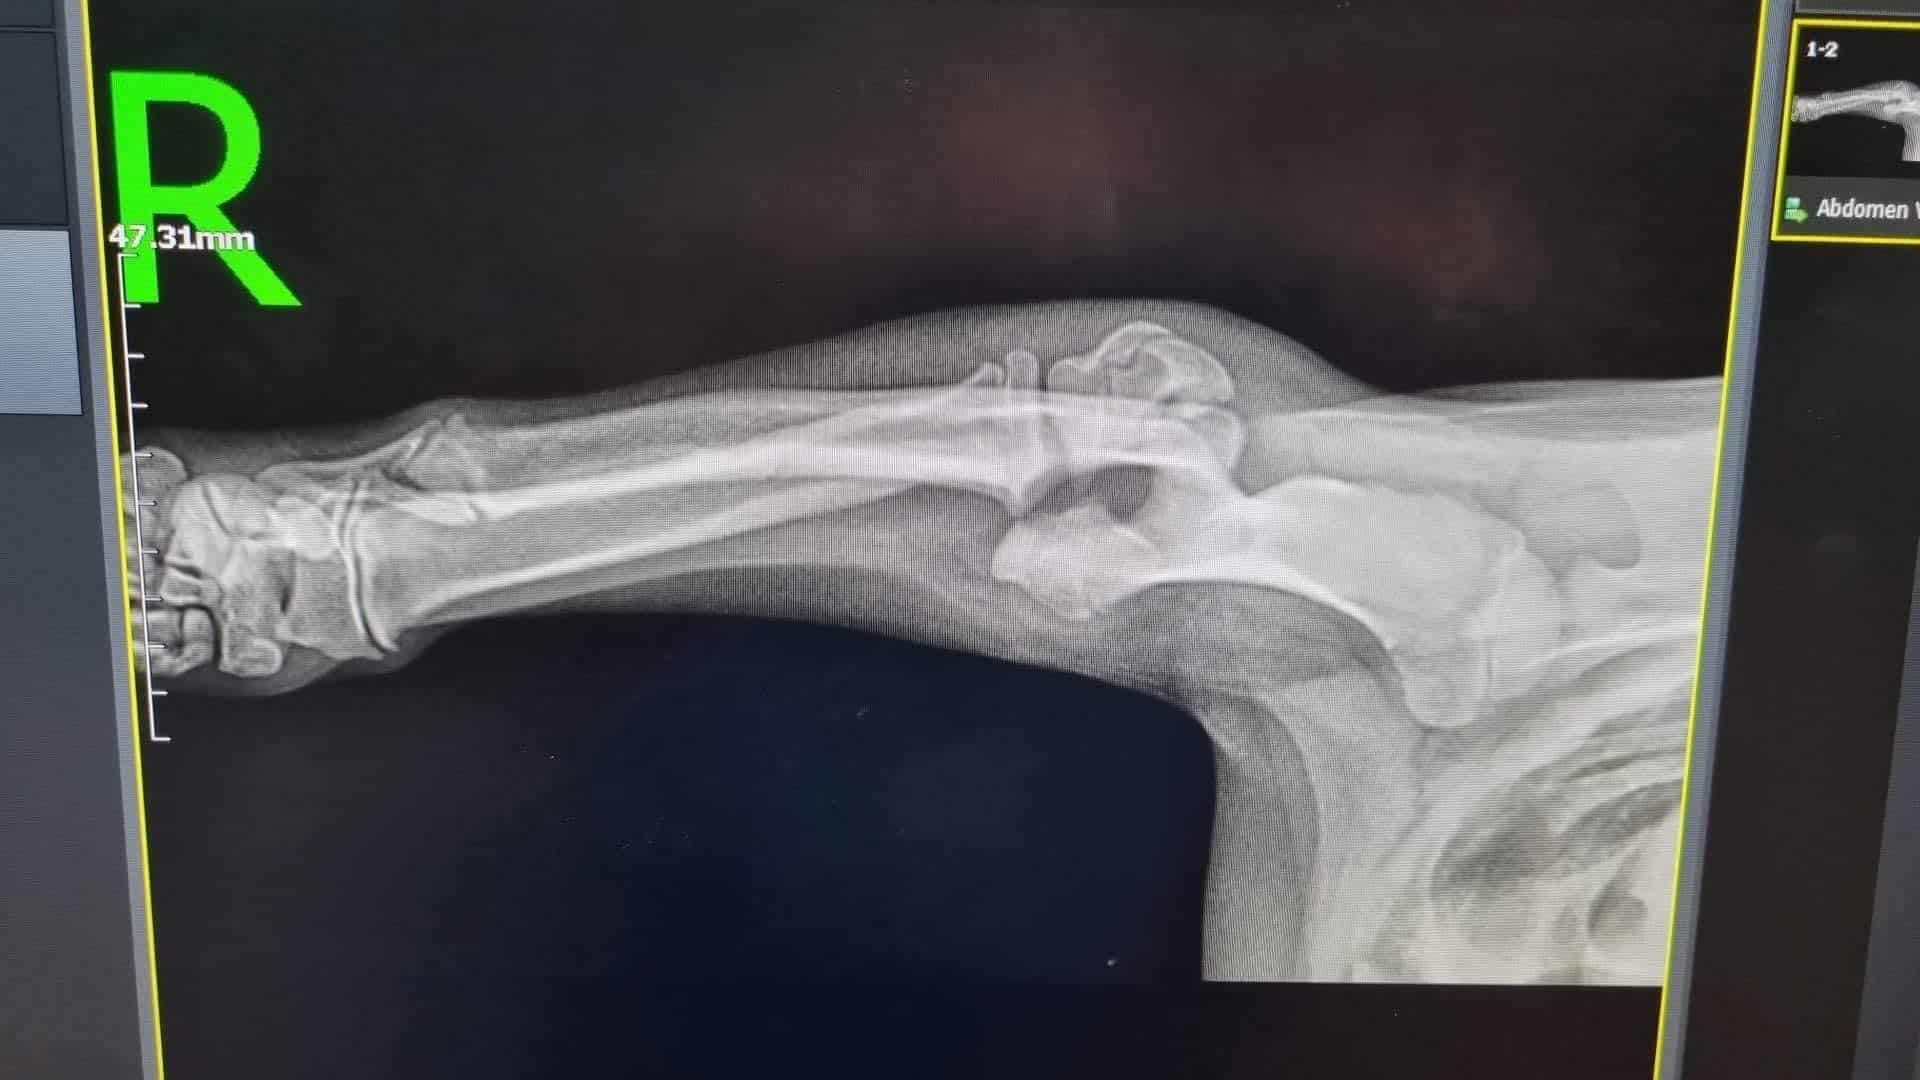

Die kleine RALUCA wurde durch ein Auto angefahren, wodurch ihr rechter Hinterlauf einen Bruch erlitt. Sie wird nun operiert und wir hoffen, dass es ihr bald besser geht und sie direkt ausreisen kann.